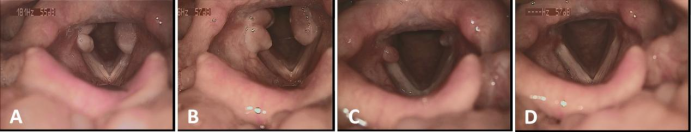

患者4次就诊时的频闪喉镜图,A为首次就诊时发现声带突肉芽肿,B为保守治疗1月后发现声带突肉芽肿变大,C为第一次电子喉镜下声带突肉芽肿处注射1月后声带突肉芽肿显著减小,D为第二次电子喉镜下声带突肉芽肿处注射1月后声带突肉芽肿消失。

陈大姐(化名)全麻手术后,咽喉部不适,声音逐渐沙哑1月,在福建医科大学附属协和医院耳鼻咽喉科行频闪喉镜检查,发现声带突肉芽肿,采用电子喉镜引导下,声带突肉芽肿注射激素药物。

1个月后,声带突肉芽肿显著减小,但仍未消失,故再次行电子喉镜引导下声带突注射,复诊发现声带突肉芽肿完全消失。